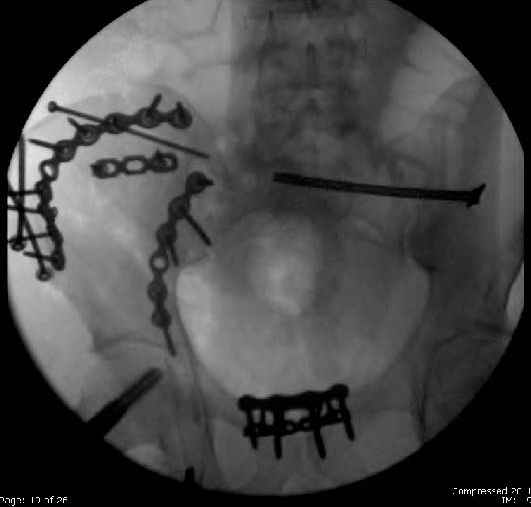

Here are the postop fluoros.

First exposed symphysis & clamped w/Faraboeuf as close to anatomic as possible.

Then extended to R ilioinguinal,really just the lateral window.

Reduced the triangular wedge piece of iliac wing to posterior intact ilium (crescent), held w/k-wire, then used 3-hole push plate to keep from moving, lagged from lat-med w 3.5 screw.

Then 6-hole plate along brim with 1 screw in R sacral ala. Then lagged 2 screws along crest A --> P. finally 10-hole plate along inner aspect of crest. R posterior ilium still a bit stepped off.

Symphysis then 'fine-tuned' & reduced as close as possible to anatomic (but, still with forward rotation of R hemipelvis - or, is it extension?) Accepted that amount of deformity and plated symph

with 4-hole symphyseal plate.

Fluoroed L SI joint and it seemed stable, but wide. So, applied c-clamp to try to squeeze down L SI joint (and note, on the last slide attached, that it's still wide), and got it closer. Single perc Iliosacral screw 40mm thread.

Applied second plate anteriorly on symphysis as I wasn't confident L SI was as stable as it could be and wanted to protect it better.

So, there I was with the aforementioned info on my mind, and my R iliac wing was a little malreduced. I think it's in residual extension and some external rotation, explaining the 5-6mm gap/step

on the posterior R iliac wing. (When I loooked at the inlet fluoro, the L obturator foramen was more visible than the R obt foramen, as was the R ischial spine) so it's not as stable as if it were

anatomic, despite all the metal. This came from hesitance to take down all the posterior paraspinals to really see the R posterior crest (where the malreduction is best seen on the iliac oblique view), and I could see the entire iliac fossa and most of the crest anyway.